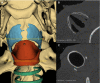

The synchronization of flight mechanics with respiration and echolocation call emission by bats, while economizing these behaviors, presumably puts compressive loads on the cartilaginous rings that hold open the respiratory tract. Previous work has shown that during postnatal development of Artibeus jamaicensis (Phyllostomidae), the onset of adult echolocation call emission rate coincides with calcification of the larynx, and the development of flight coincides with tracheal ring calcification. In the present study, I assessed the level of reinforcement of the respiratory system in 13 bat species representing six families that use stereotypical modes of echolocation (i.e. duty cycle % and intensity). Using computed tomography, the degree of mineralization or ossification of the tracheal rings, cricoid, thyroid and arytenoid cartilages were determined for non-echolocators, tongue clicking, low-duty cycle low-intensity, low-duty cycle high-intensity, and high-duty cycle high-intensity echolocating bats. While all bats had evidence of cervical tracheal ring mineralization, about half the species had evidence of thoracic tracheal ring calcification. Larger bats (Phyllostomus hastatus and Pterpodidae sp.) exhibited more extensive tracheal ring mineralization, suggesting an underlying cause independent of laryngeal echolocation. Within most of the laryngeally echolocating species, the degree of mineralization or ossification of the larynx was dependent on the mode of echolocation system used. Low-duty cycle low-intensity bats had extensively mineralized cricoids, and zero to very minor mineralization of the thyroids and arytenoids. Low-duty cycle high-intensity bats had extensively mineralized cricoids, and patches of thyroid and arytenoid mineralization. The high-duty cycle high-intensity rhinolophids and hipposiderid had extensively ossified cricoids, large patches of ossification on the thyroids, and heavily ossified arytenoids. The high-duty cycle high-intensity echolocator, Pteronotus parnellii, had mineralization patterns and laryngeal morphology very similar to the other low-duty cycle high-intensity mormoopid species, perhaps suggesting relatively recent evolution of high-duty cycle echolocation in P. parnellii compared with the Old World high-duty cycle echolocators (Rhinolophidae and Hipposideridae). All laryngeal echolocators exhibited mineralized or ossified lateral expansions of the cricoid for articulation with the inferior horn of the thyroid, these were most prominent in the high-duty cycle high-intensity rhinolophids and hipposiderid, and least prominent in the low-duty cycle low-intensity echolocators. The non-laryngeal echolocators had extensively ossified cricoid and thyroid cartilages, and no evidence of mineralization/ossification of the arytenoids or lateral expansions of the cricoid. While the non-echolocators had extensive ossification of the larynx, it was inconsistent with that seen in the laryngeal echolocators.